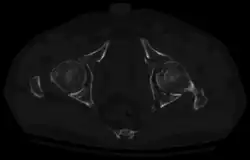

X-ray visualization is best done in Antero posterior view and Iliac and obturator oblique views. In CT scan the characteristic feature is that the fracture line runs from front to back. CT scan also helps in identifying impaction of bone pieces and if there are pieces in the joint

To understand the fracture pattern of a fractured acetabulum, it is essential to have minimum three x-ray views, though use of CT scan with 3-D reconstruction of images has made understanding of these fractures easier.

1. Pelvis with both hips antero posterior view. This view shows six important landmarks of the acetabulum, specifically: